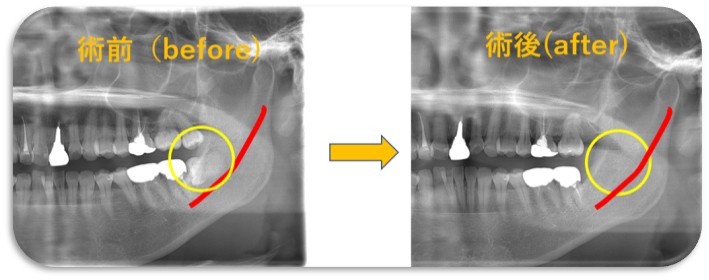

親知らず抜歯に関しては上下、骨に埋まってる難しい歯を含めて多数の症状に対応可能となっており、大和市内市外からも患者さんが来られるそうです。